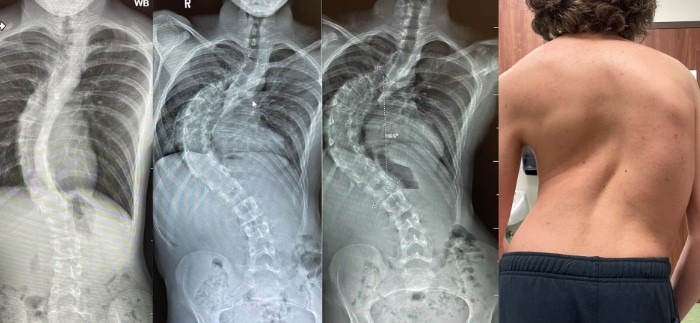

اسکولیوز یا انحراف ستون فقرات، به انحنای غیرطبیعی ستون فقرات به طرفین اطلاق می‌شود که به شکل “S” یا “C” دیده می‌شود. این وضعیت می‌تواند در هر سنی رخ دهد، اما معمولاً در دوران کودکی یا نوجوانی تشخیص داده می‌شود. علل اسکولیوز متنوع بوده و شامل عوامل ژنتیکی، عصبی-عضلانی، مادرزادی و محیطی می‌باشند. در ادامه به بررسی دقیق‌تر این علل می‌پردازیم.

عکس انحراف ستون فقرات